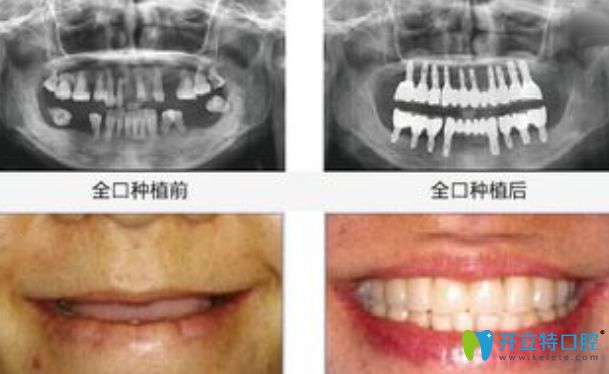

全口種植牙前后對(duì)比圖